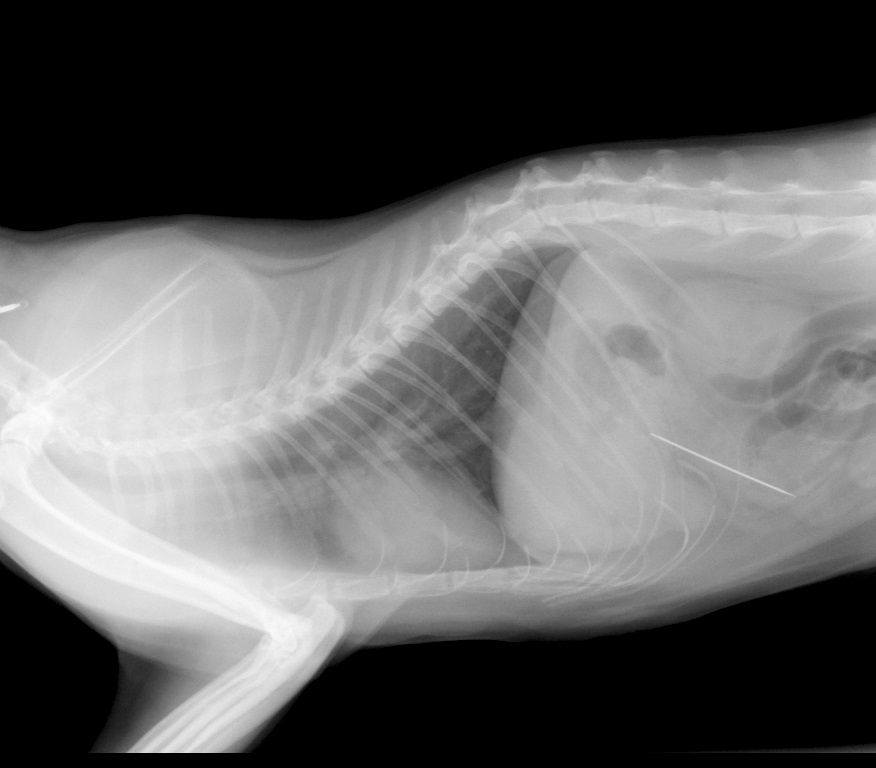

Op de röntgenfoto die wij vervolgens maakte bleek dat de naald in ieder geval door Kitty was doorgeslikt.....een spoedoperatie was het gevolg. Zie hier de foto's.

Röntgenfoto van Kitty

Een klein puntje verraadt de naald: hij zit inmiddels in de dunne darm!